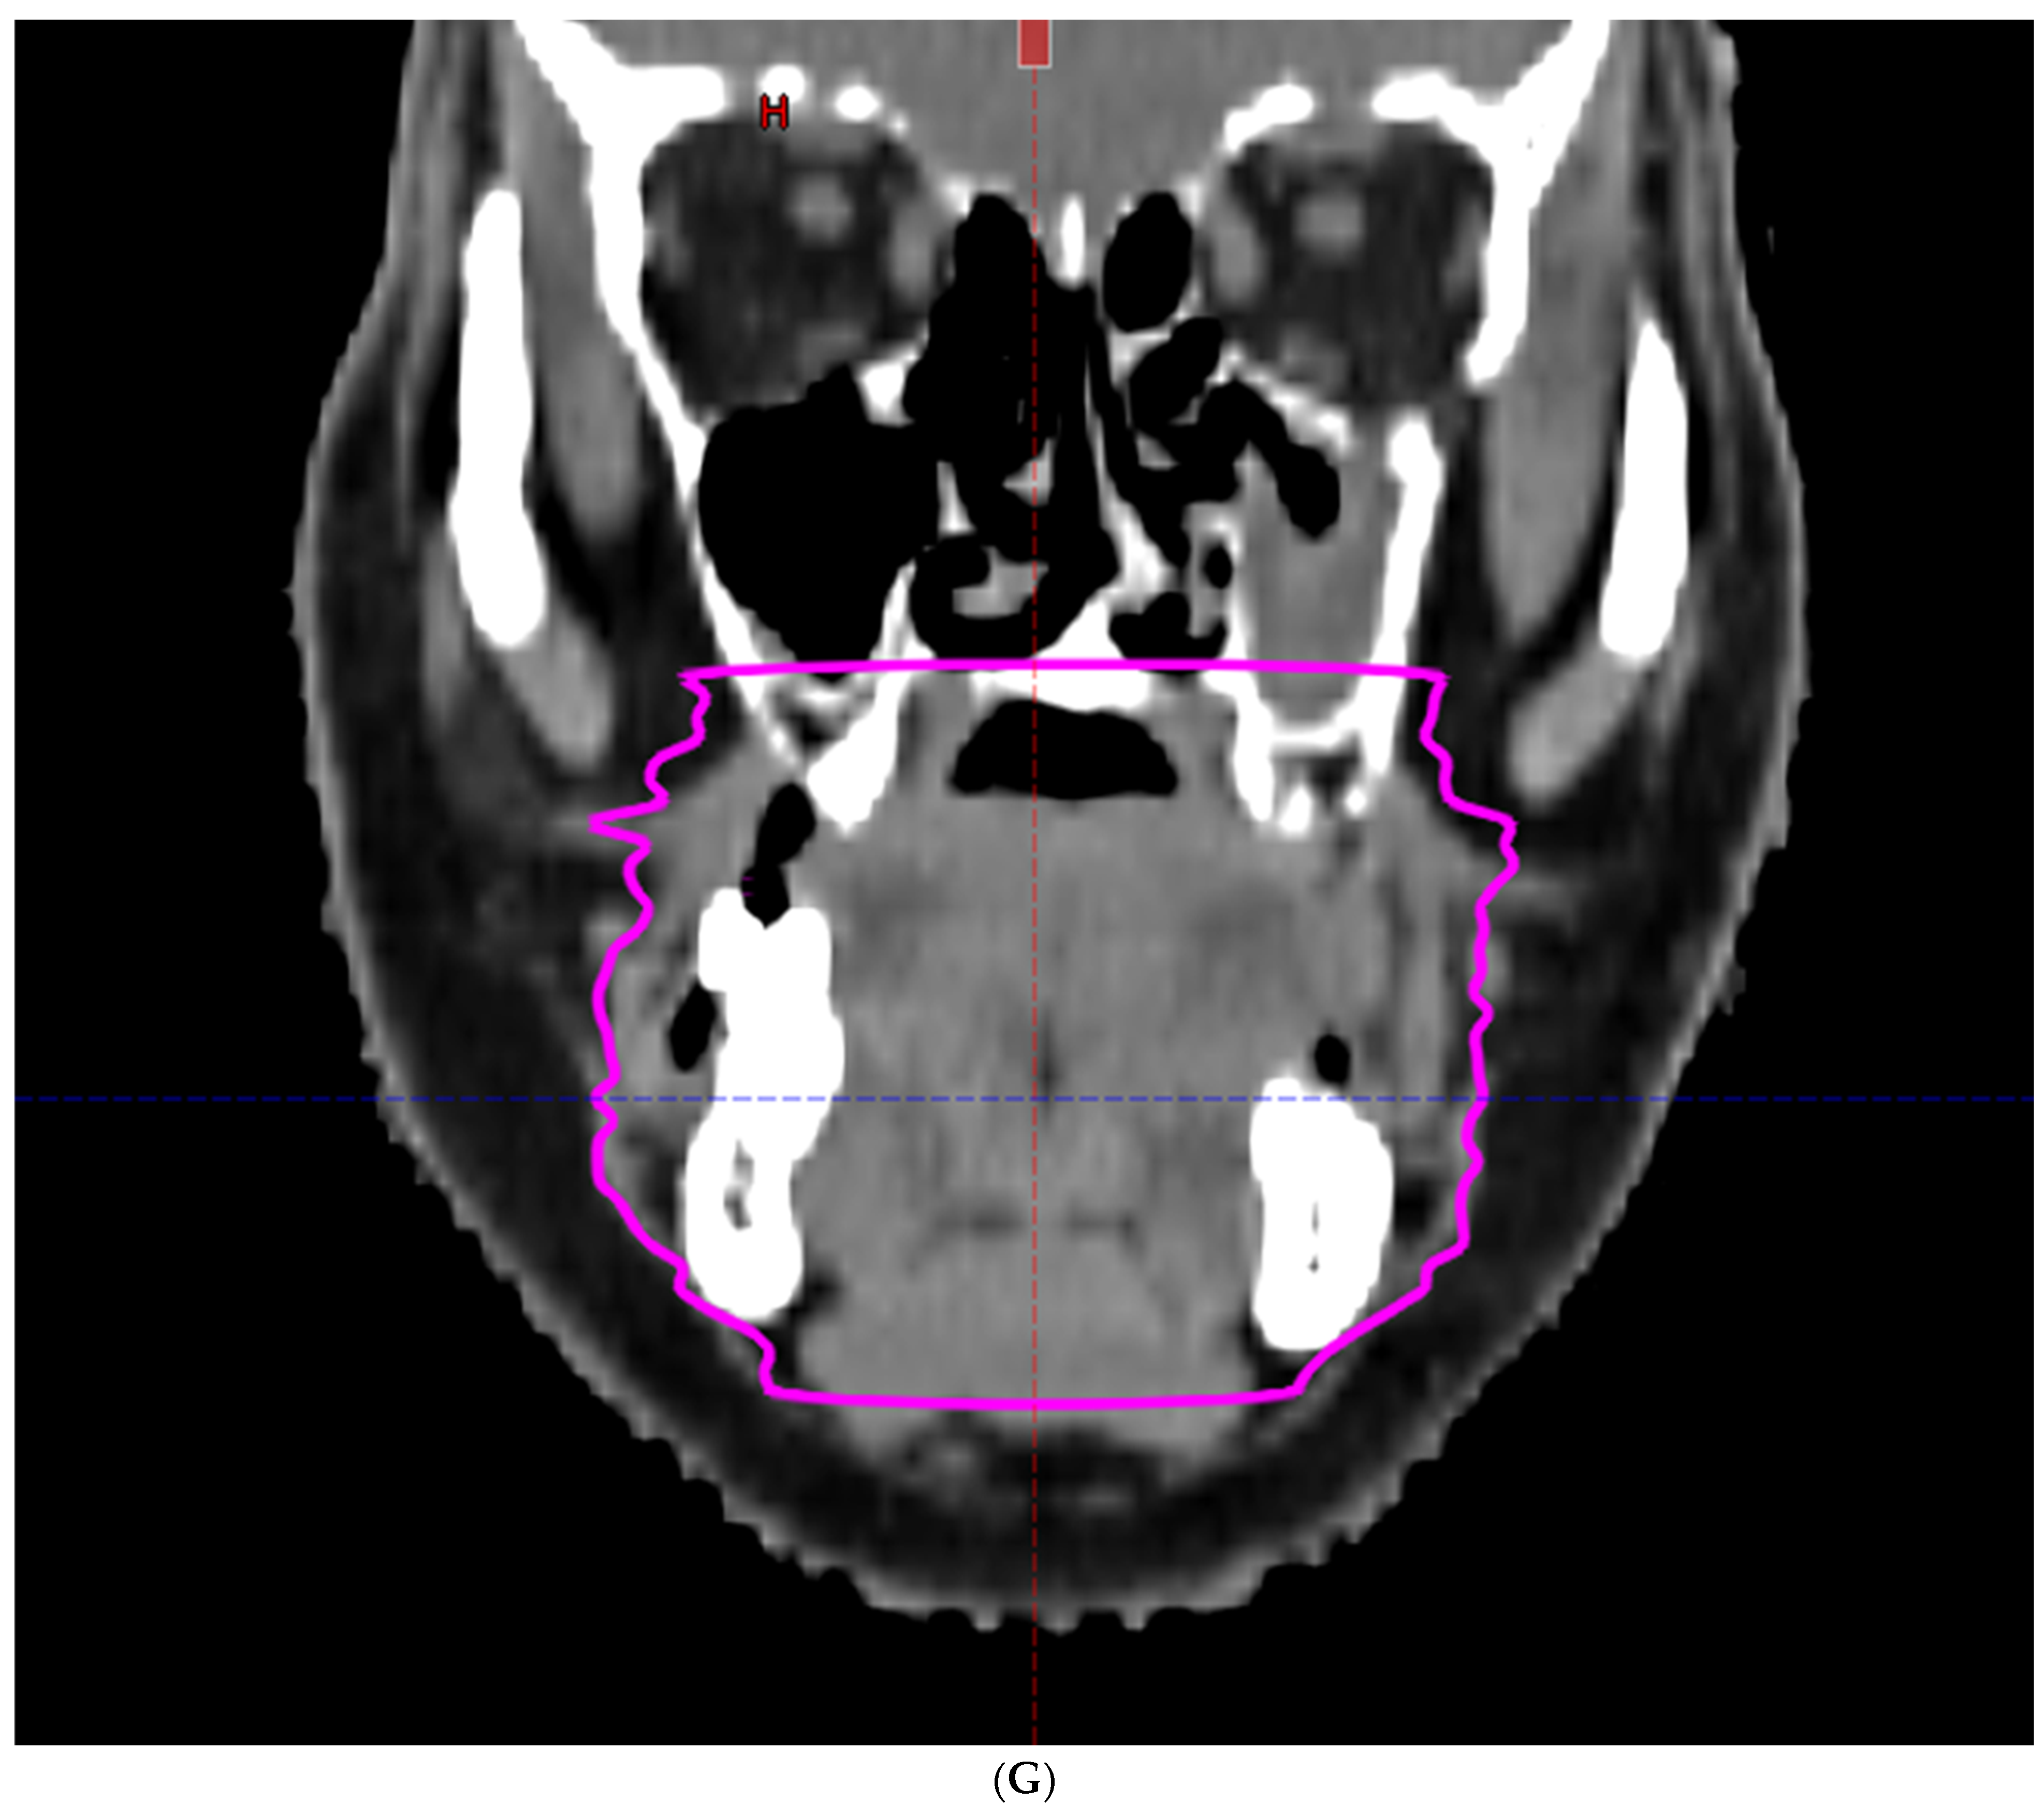

- Hoebers, F.; Yu, E.; Thorstad, W.; O’Sullivan, B.; Dawson, L.A.; Hope, A. A Pragmatic Contouring Guideline for Salivary Gland Structures in Head and Neck Radiation Oncology. The MOIST Target. Am. J. Clin. Oncol. 2013, 36, 70–76. [Google Scholar] [CrossRef]

- Brouwer, C.L.; Steenbakkers, R.J.; Bourhis, J.; Budach, W.; Grau, C.; Grégoire, V.; Van Herk, M.; Lee, A.; Maingon, P.; Nutting, C.; et al. CT-based delineation of organs at risk in the head and neck region: DAHANCA, EORTC, GORTEC, HKNPCSG, NCIC CTG, NCRI, NRG Oncology and TROG consensus guidelines. Radiother. Oncol. 2015, 117, 83–90. [Google Scholar] [CrossRef]

- Li, K.; Yang, L.; Hu, Q.-Y.; Chen, X.-Z.; Chen, M.; Chen, Y. Oral Mucosa Dose Parameters Predicting Grade ≥ 3 Acute Toxicity in Locally Advanced Nasopharyngeal Carcinoma Patients Treated with Concurrent Intensity-Modulated Radiation Therapy and Chemotherapy: An Independent Validation Study Comparing Oral Cavity versus Mucosal Surface Contouring Techniques. Transl. Oncol. 2017, 10, 752–759. [Google Scholar] [CrossRef]

- Sun, Y.; Yu, X.-L.; Luo, W.; Lee, A.W.; Wee, J.T.S.; Lee, N.; Zhou, G.-Q.; Tang, L.-L.; Tao, C.-J.; Guo, R.; et al. Recommendation for a contouring method and atlas of organs at risk in nasopharyngeal carcinoma patients receiving intensity-modulated radiotherapy. Radiother. Oncol. 2014, 110, 390–397. [Google Scholar] [CrossRef]

- Dean, J.A.; Welsh, L.C.; Gulliford, S.L.; Harrington, K.J.; Nutting, C.M. A novel method for delineation of oral mucosa for radiotherapy dose–response studies. Radiother. Oncol. 2015, 115, 63–66. [Google Scholar] [CrossRef]